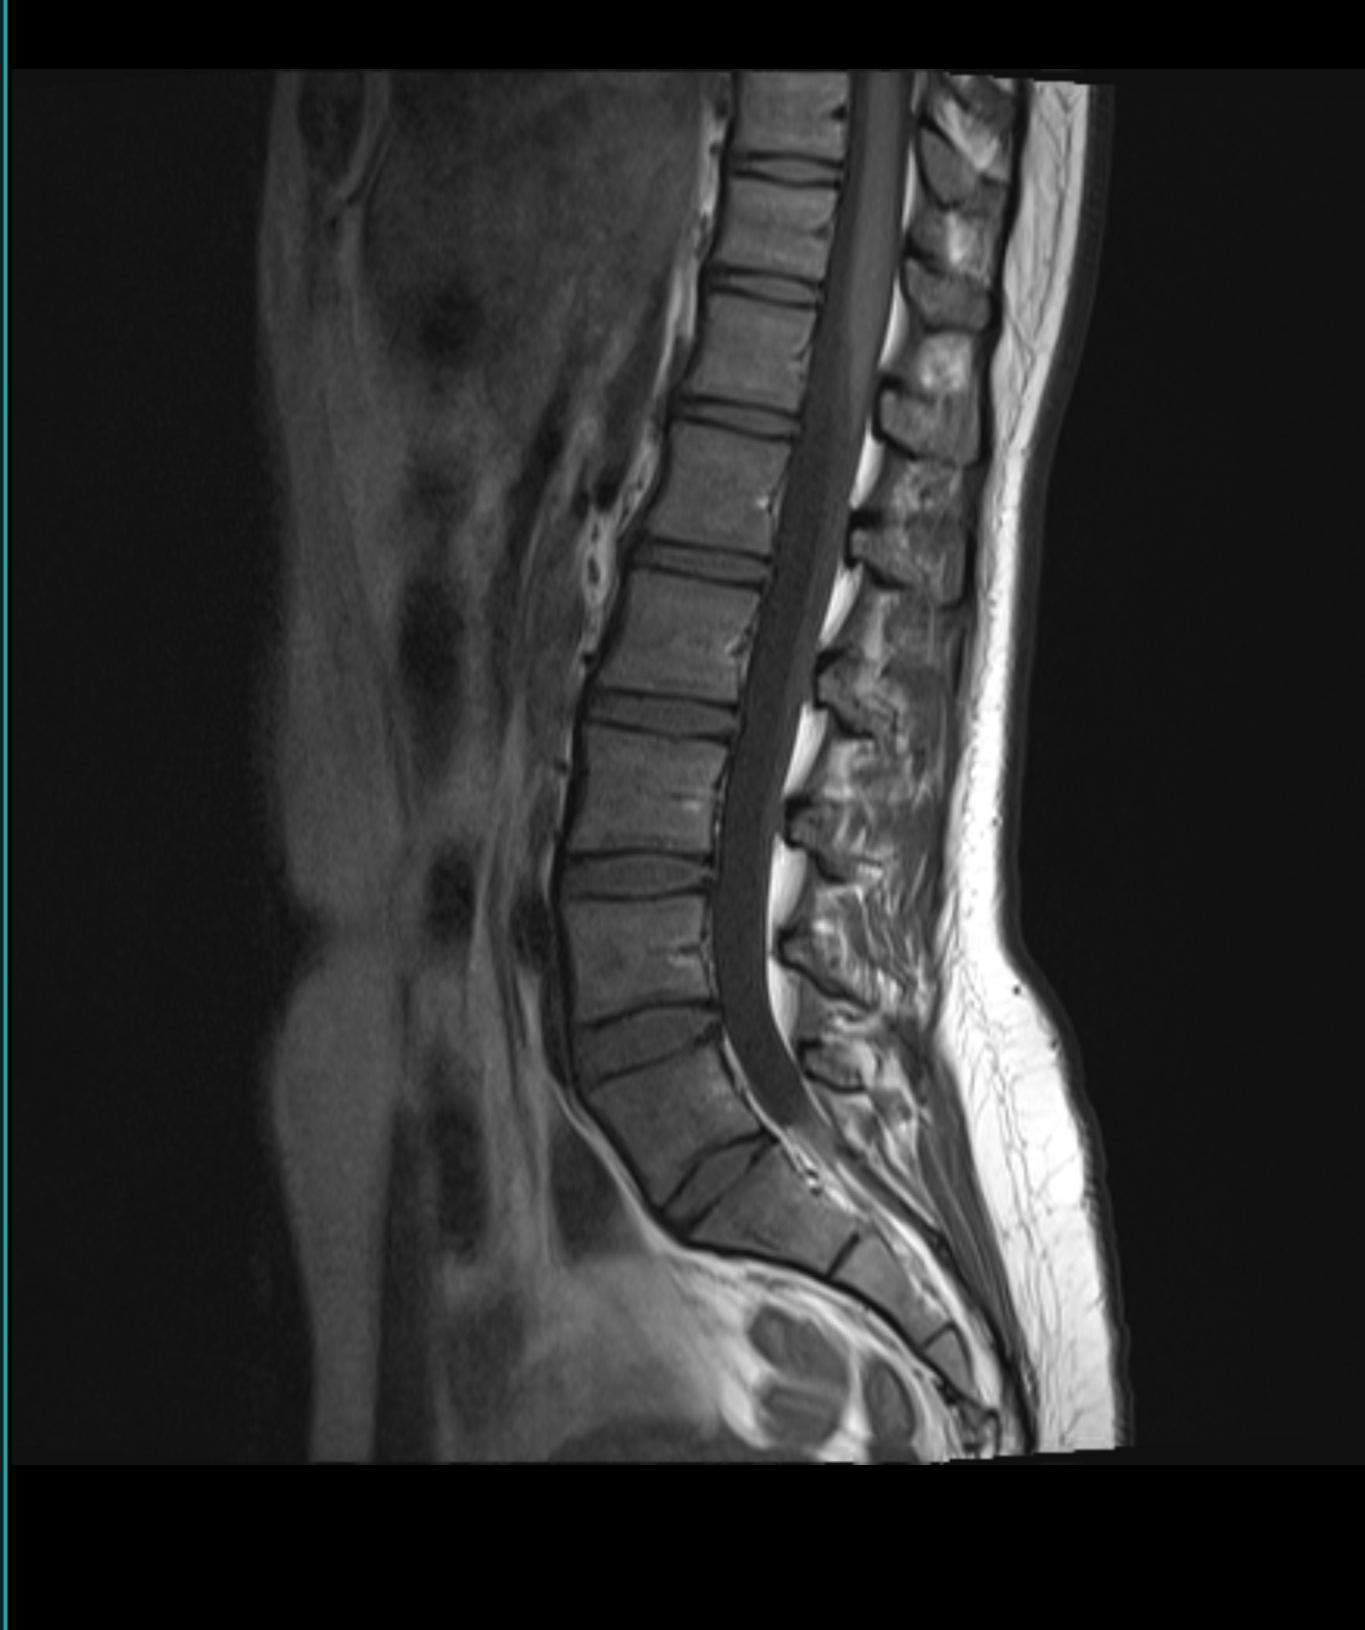

„Ich möchte mich ganz herzlich für Ihre umfangreiche Übersetzung des MRT-Berichtes bedanken. Sie haben eine hervorragende Dokumentation in Wort und Bild angefertigt, die auch für einen Laien sehr verständlich ist. Ich werde bei meinen nächsten Arztbesuch daher entscheidende Fragen für den weiteren Fortgang der Behandlung stellen.. AW: MRT Befund - Übersetzung für Laien. flache linkskonvexe Einstellung: in der Aufsicht von hinten ist die Wirbelsäule leicht nach links gebogen (=Skoliose) Das haben viele Menschen, bei einem Winkel unter 10° ist das nichts Schlimmes. lumbosakrale Übergangsanomalie: im Übergang von der LWS zum Steißbein gibt es eine Fehlstellung.